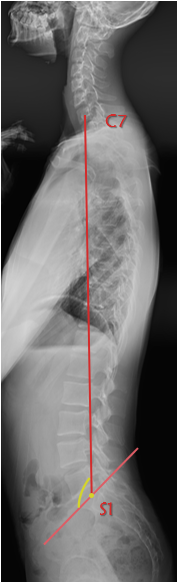

7. 矢状面垂直轴(SVA/SVAO)

矢状面垂直轴定义为从C7垂直线到S1后角的偏移量。SVA的正常范围尚未确定,可能介于前2.5cm后5.0cm之间。矢状面垂直轴(SVA/SVAO)常用于判断脊柱矢状位有无失衡的一个重要指标。

8. 脊柱-骶骨角(SSA)

脊柱-骶骨角:C7中点与S1上终板中点的连线与骶骨上终板所形成的夹角。SSA的正常范围:134.7± 8°,是评估矢状位平衡的重要指标。